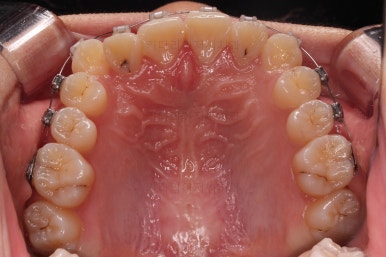

입 안을 보면 밑에 치열이나 다른 부분은 비교적 양호한데 유달리 윗니 송곳니만 위치가 좋지 못하네요.

충치가 곳곳에 보이는데요.

성인들은 충치가 멈춰있는 정지우식일 가능성도 있으며 크기가 현재 크지 않고 향후 변화되지 않는다면 그대로 두기도 합니다.

이번 환자분도 교정치료에 방해되는 부분이나 급해보이는 추료만 우선 진행하고 교정 중에 충치가 커지는지 증상이 생기는지 관찰해 보기로 했습니다.

연산동교정치과 교정장치 부착 직후의 모습입니다.